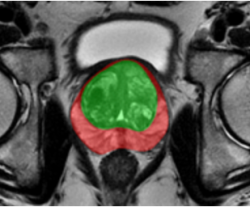

NVFlare and its predecessors have been used in several real-world studies exploring FL for healthcare scenarios. The collaborations between multinational institutions tested and validated the utility of federated learning, pushing the envelope for training robust, generalizable AI models. These initiatives included FL for breast mammography classification [32], prostate segmentation [33], pancreas segmentation [37], and most recently, chest X-ray (CXR) and electronic health record (EHR) analysis to predict the oxygen requirement for patients arriving in the emergency department with symptoms of COVID-19 [6].